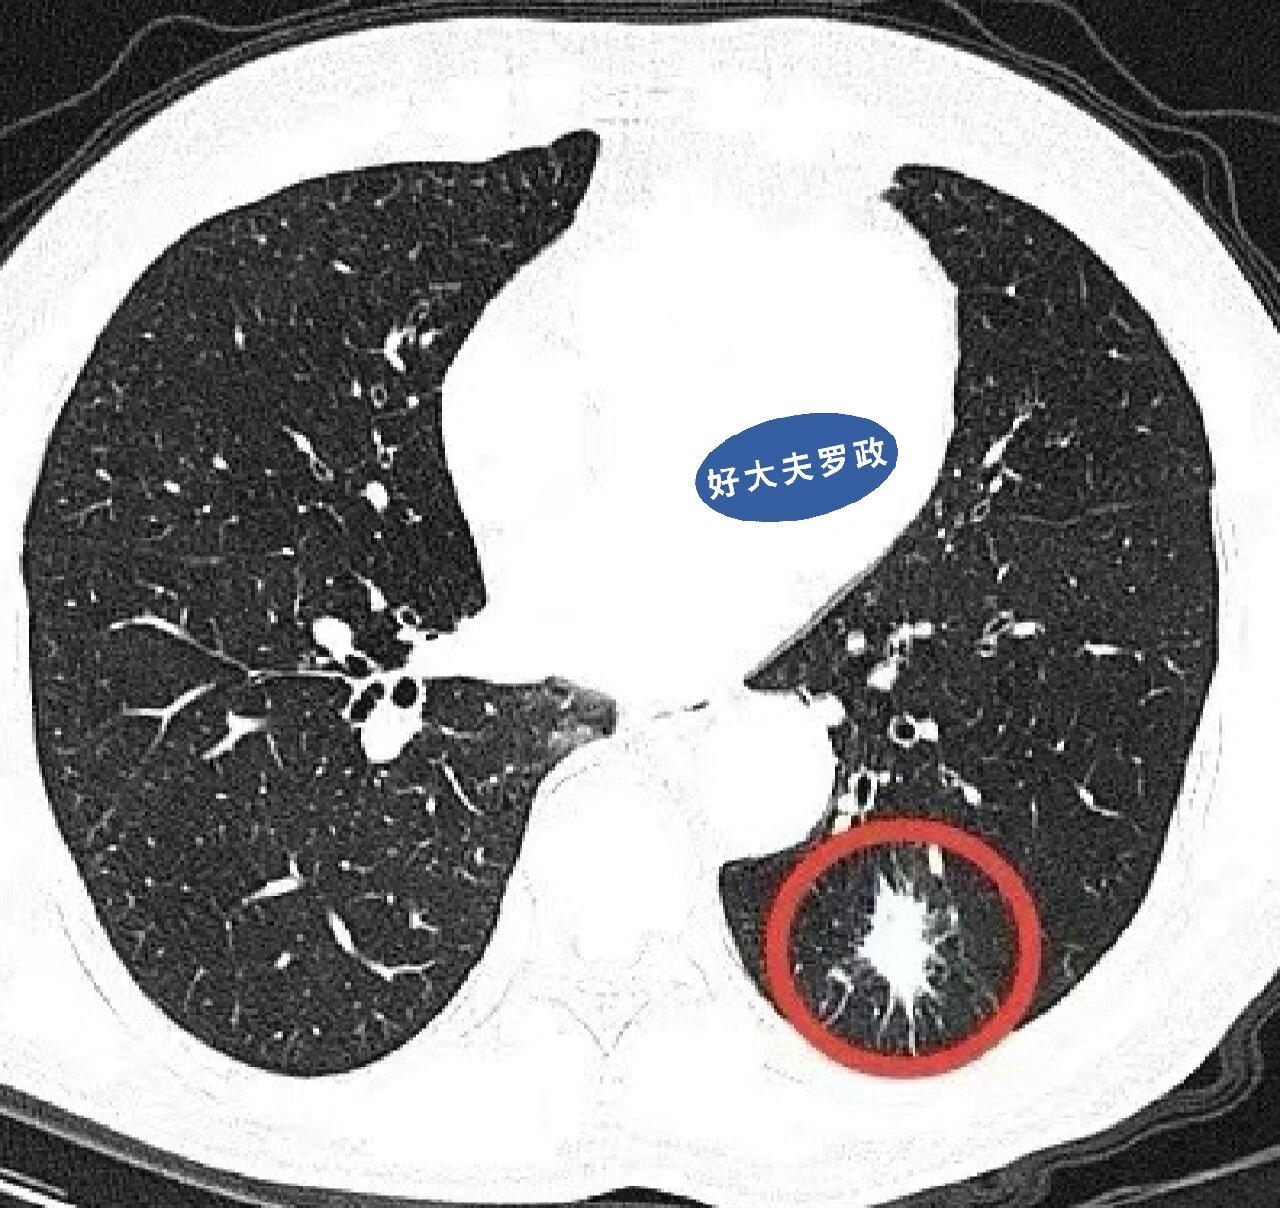

具有以下特征的肺结节,可能是恶性的,一定要警惕. 1,毛刺征

图片尺寸934x1024